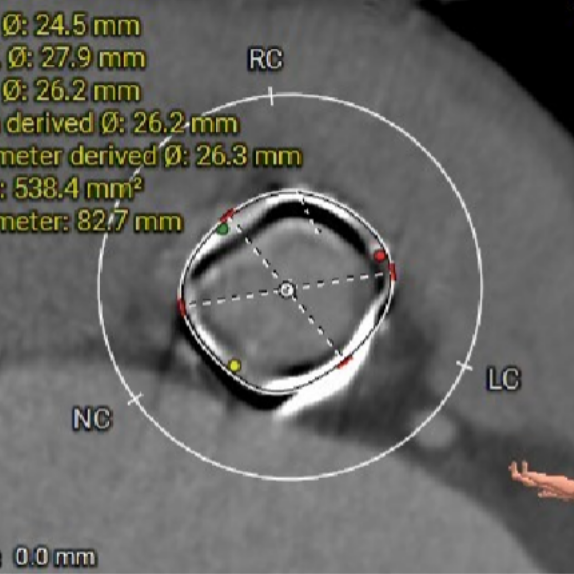

术前CT评估-TMVI viv

二尖瓣瓣环——内径

二尖瓣瓣环——外径

选瓣依据:该二尖瓣原置换生物瓣为Hancoke II#31 ,CT测量生物瓣瓣环周长折算直径约28.0mm,瓣架高度约19.1mm;